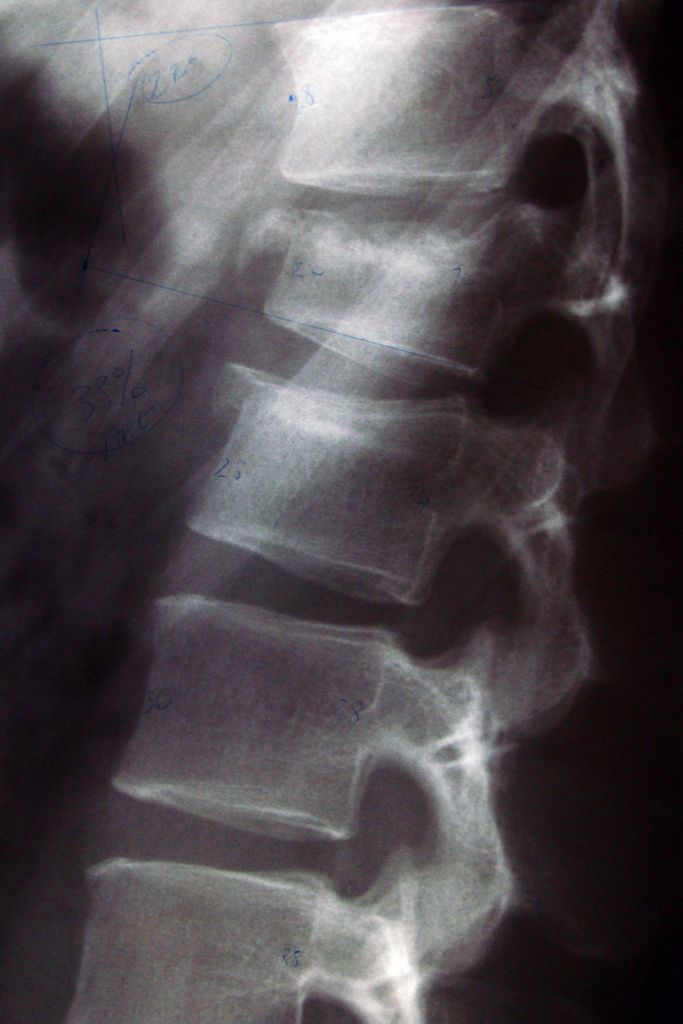

/ 14Osteoporoza - uszkodzenie kręgosłupa

Obraz

Osteoporoza a uszkodzenie kręgosłupa

Uszkodzenie kręgosłupa powoduje niezwykle silny ból, który promieniuje od tyłu w kierunku boków. Z biegiem czasu powtarzające się uszkodzenia kręgosłupa mogą wywołać przewlekłe bóle dolnej części pleców, obniżenie wzrostu lub powstanie garbu.